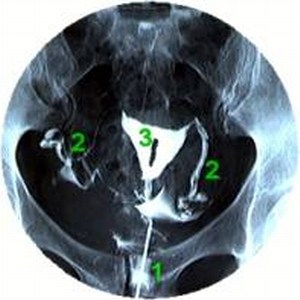

HSG (Hysterosalpingographia)

A HSG tulajdonképpen nem más, mint Rtg. kontrasztanyag befecskendezése

a méhnyakon át a méh üregébe, ami onnan a kürtökön keresztül a hasüregbe jut.

Mindezt Röntgen-átvilágító készülékkel nyomon tudja követni a vizsgálatot végző

orvos. Segít a méhüreg és a kürtök állapotának megítélésében.

1. a kontrasztanyag be- fecskendezése 2. kürtök 3. méh |

Egészséges esetben a méh ürege normális, a kürtök alakja

és átjárhatósága megfelelő és a kontrasztanyag szabadon kijut mindkét oldalon

a hasüregbe. A méh egyes eltérései jól diagnosztizálhatók: